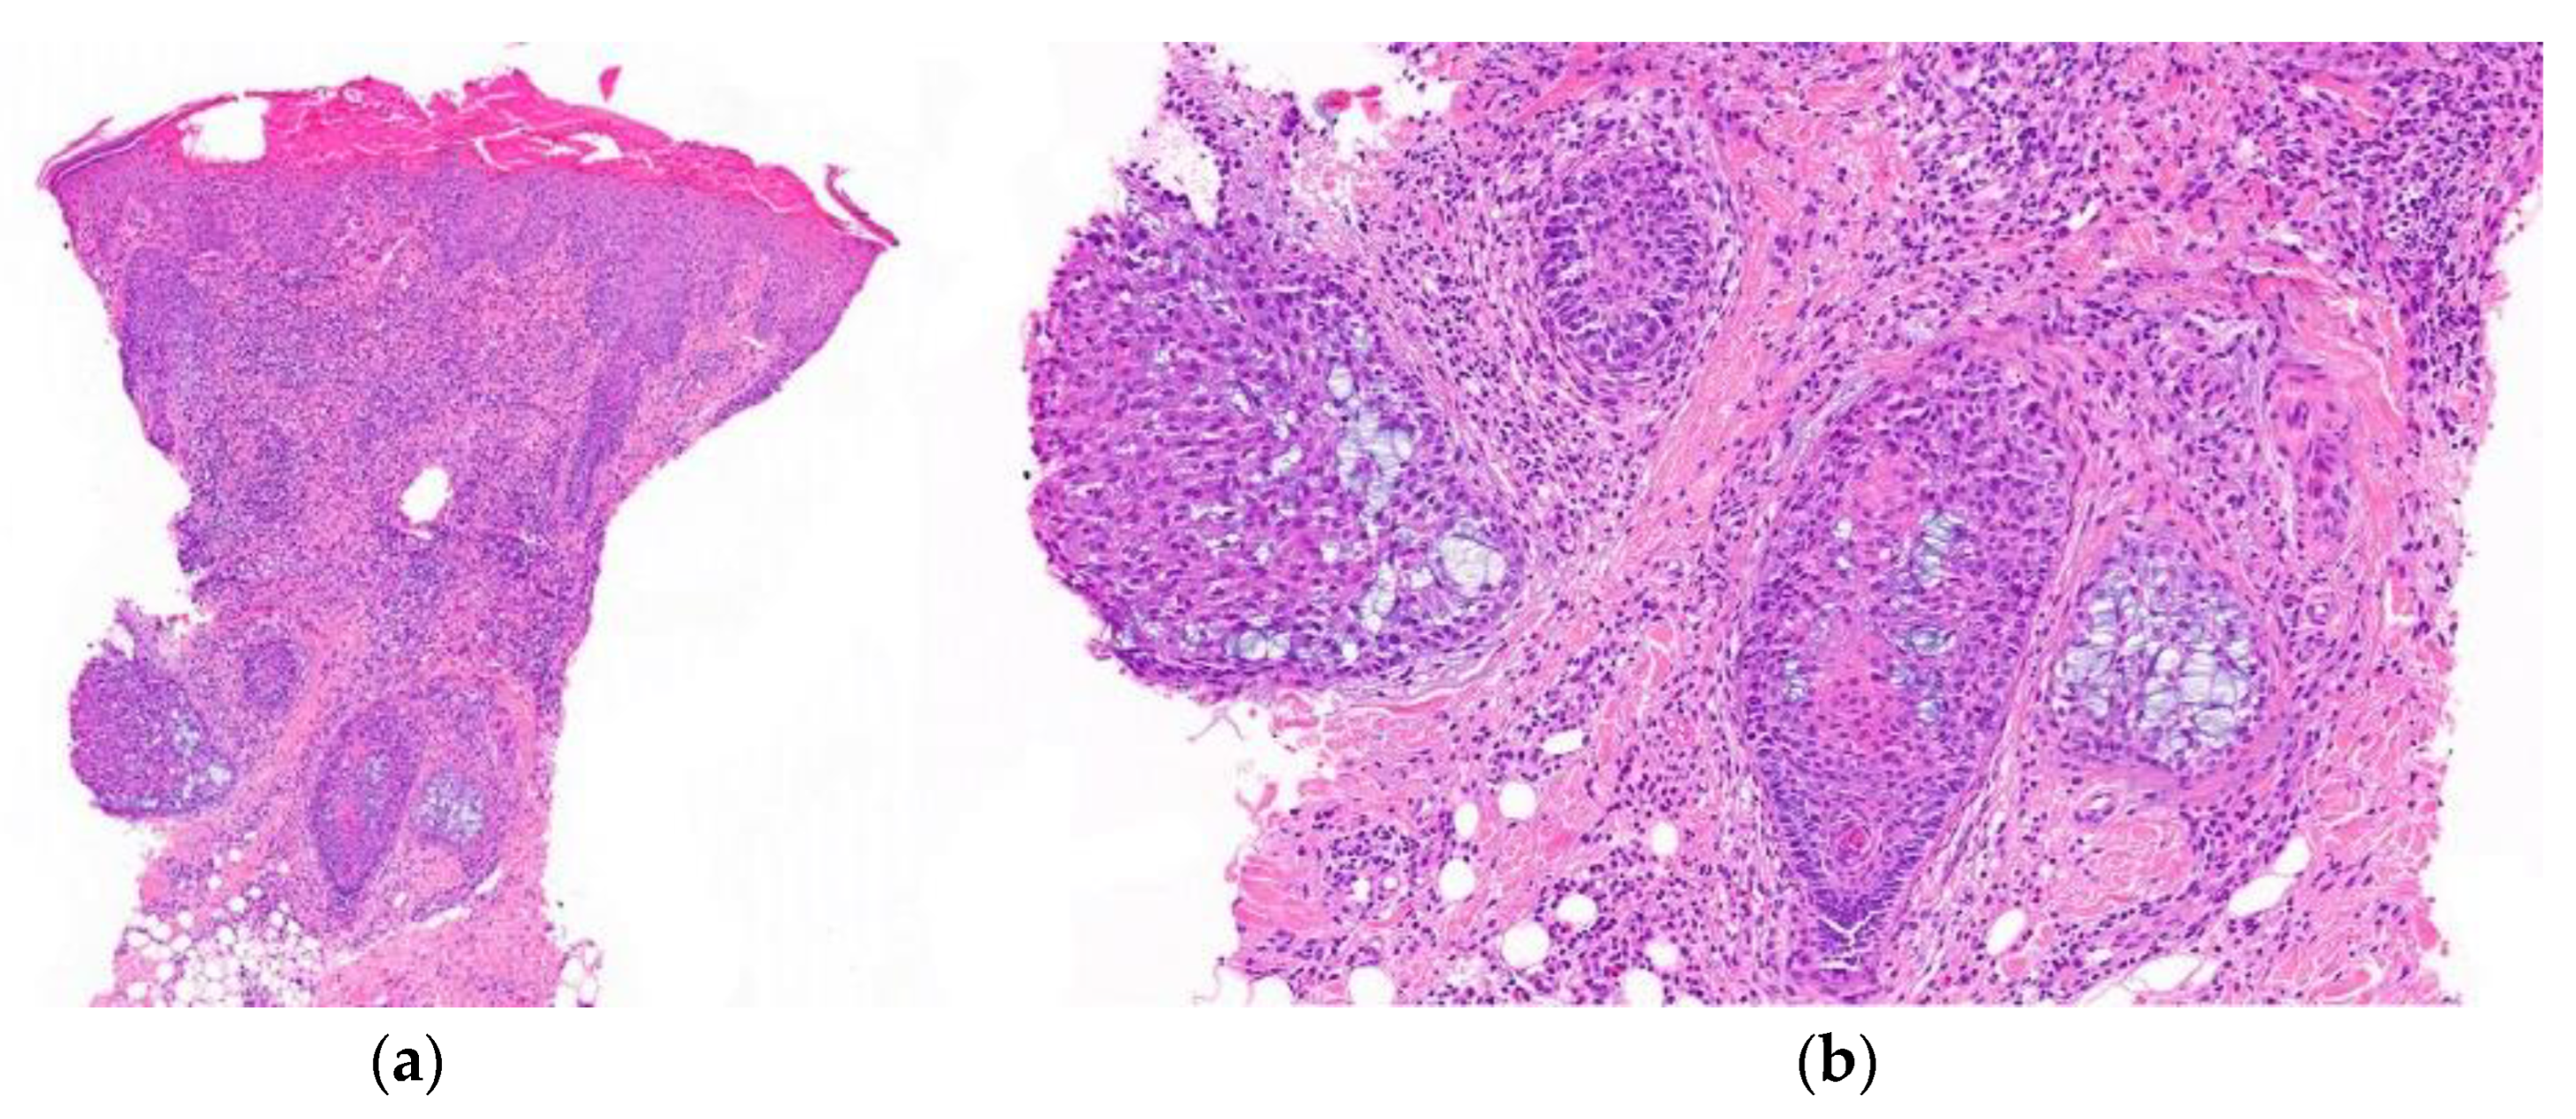

- Histological Features (Figure 9):

- -

- Peribulbar inflammatory infiltrate: during the active phase of alopecia areata, a characteristic peribulbar inflammatory infiltrate is seen around the anagen (growth) hair follicles (“swarm of bees”).

- Apoptosis of matrix cells within the hair follicle can be observed.

- Presence of lymphocytes, eosinophils, and melanin in follicular streamers (inactive phase). Utility of CD3 staining.

- Increase in vellus index.

- Increase in telogen index.